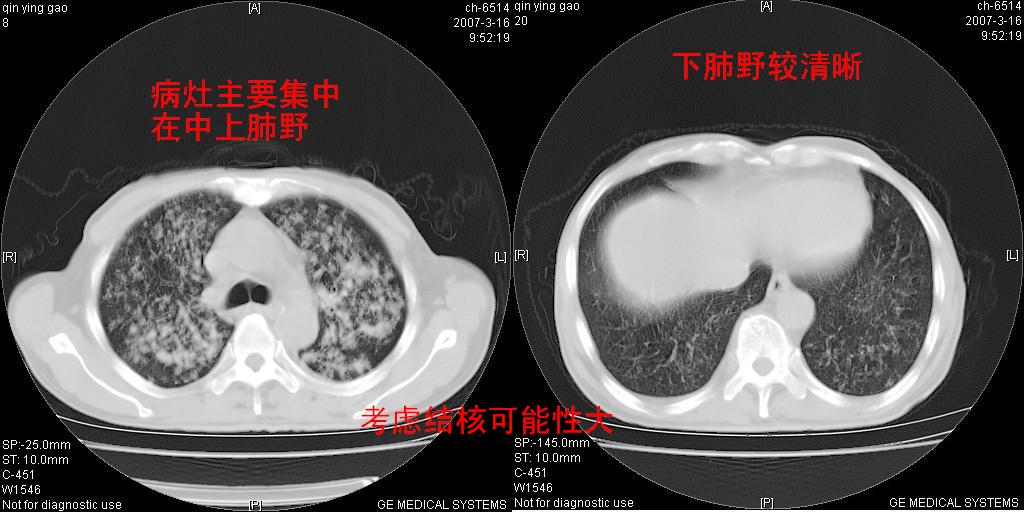

两中上肺见有广泛新老不一的结节灶,并伴有纤维索条影,血沉加快,白细胞不高,首先考虑结核。

双肺可见大小不等结节状密度增高影,密度不均,分布不均(双肺上叶为著),亚急性血行播散性肺结核.

(本例特征:以大小不等结节为主,主要分布在双上肺,并部分病灶融合成较大结节,期间搀杂诸多细小结节。从病灶特点与分布形式分析,更趋向于感染。)

考虑结核可能性大,因为病变是沿肺纹理走行发展的。

我觉得应该是结核,支气管肺泡癌多以双肺中下野多见,结核上野多见

两中上肺见有广泛分布大小不一的结节灶及斑片状影,部分融合,双下肺未见异常密度影,纵隔无明显肿大淋巴结,血沉加快,白细胞不高,首先考虑结核。 建议结合ppd检查或痰培养排除其他非特异性炎症。

中上肺野密布棉团状影,以胸膜下区为界,边缘模糊,可能是小叶或腺泡渗出及实变。全肺野弥漫分布网线样影及细小粟粒样影,可能是细支气管炎及间质内炎症。综合分析应首先考虑气道播散性感染,而肺内多处斑点性钙化,强烈提示陈旧结核复发并支气管播散。建议详细讯问病史

病变以两肺上野为著,部分病灶有钙化,纵隔窗显示病灶有新老不一,这个首先和结核脱不了干系,还有部分病灶有融洽的倾向,肿瘤也不能完全排出